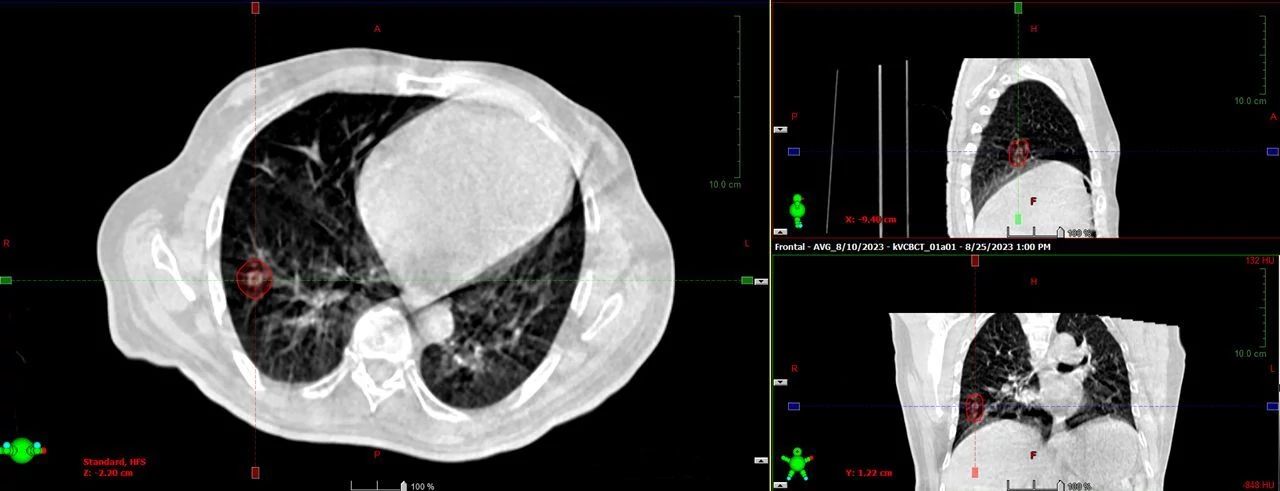

HyperSight brings fast, highly accurate imaging into the treatment room. It enables the acquisition of cone-beam CT (CBCT) images in as little as six seconds, with the Hounsfield Unit (HU) accuracy required for calculating dose distributions directly on the images. The HyperSight image reconstruction algorithms, combined with the expanded field of view (FOV) offer improved visualization of larger areas of interest often encompassing the entire target volume and surrounding organs at risk (OARs). HyperSight is now available as an optional feature on Varian’s Halcyon, Ethos, TrueBeam, and Edge radiotherapy systems.

HyperSight images show how radiotherapy treatment and physiological processes such as weight loss are impacting the tumor and surrounding anatomy over a course of treatment. The enhanced-quality HyperSight CBCT images generated right in the treatment vault make it possible to more easily compensate for any changes to the tumor and nearby organs. Previously, processes for adapting to such changes often required a new CT scan on a separate machine.

Clinicians at Icon Cancer Centre Holmesglen also use HyperSight imaging to streamline replanning decisions for patients on treatment. “When we see changes in volumes or contours, we are able to quickly run a calculation on the CBCT showing dose distributions for quicker decisions about whether to go ahead and treat or to stop and rescan,” says Sarah Hauville, Radiation Therapy Manager.

A dedicated CT scanner for Radiation Oncology is in the plans, but in the meantime, as needed, HyperSight CBCTs are used for treatment planning. “In a hospital system where we have limited resources and space, we want to offer the best care we can by optimizing our internal department procedures. HyperSight is a great solution for us, so that we aren’t completely dependent on Radiology,” says Alvin Khan, PhD, DABR, Director of Clinical Physics. “It has improved our throughput and our clinical staff experience.”

Like St. Joseph’s Medical Center, the Icon Cancer Centre Holmesglen also relies on the hospital CT scanner. “The Radiology Department is very busy because they also handle emergency patients, so we have limited access to the CT scanner,” says Hauville. With no footprint for a diagnostic CT scanner dedicated to radiation oncology, Icon Holmesglen upgraded its Halcyon system with HyperSight imaging in March 2023. This upgrade gave the Icon clinical team the ability to simulate and plan for prostate, rectum, and gynecological treatments in their own department. “Since we started utilizing HyperSight for planning, our clinicians have been very satisfied with the ability to accurately contour volumes and calculate dose distribution on the images,” reports Peter Phung, Senior Medical Physicist.